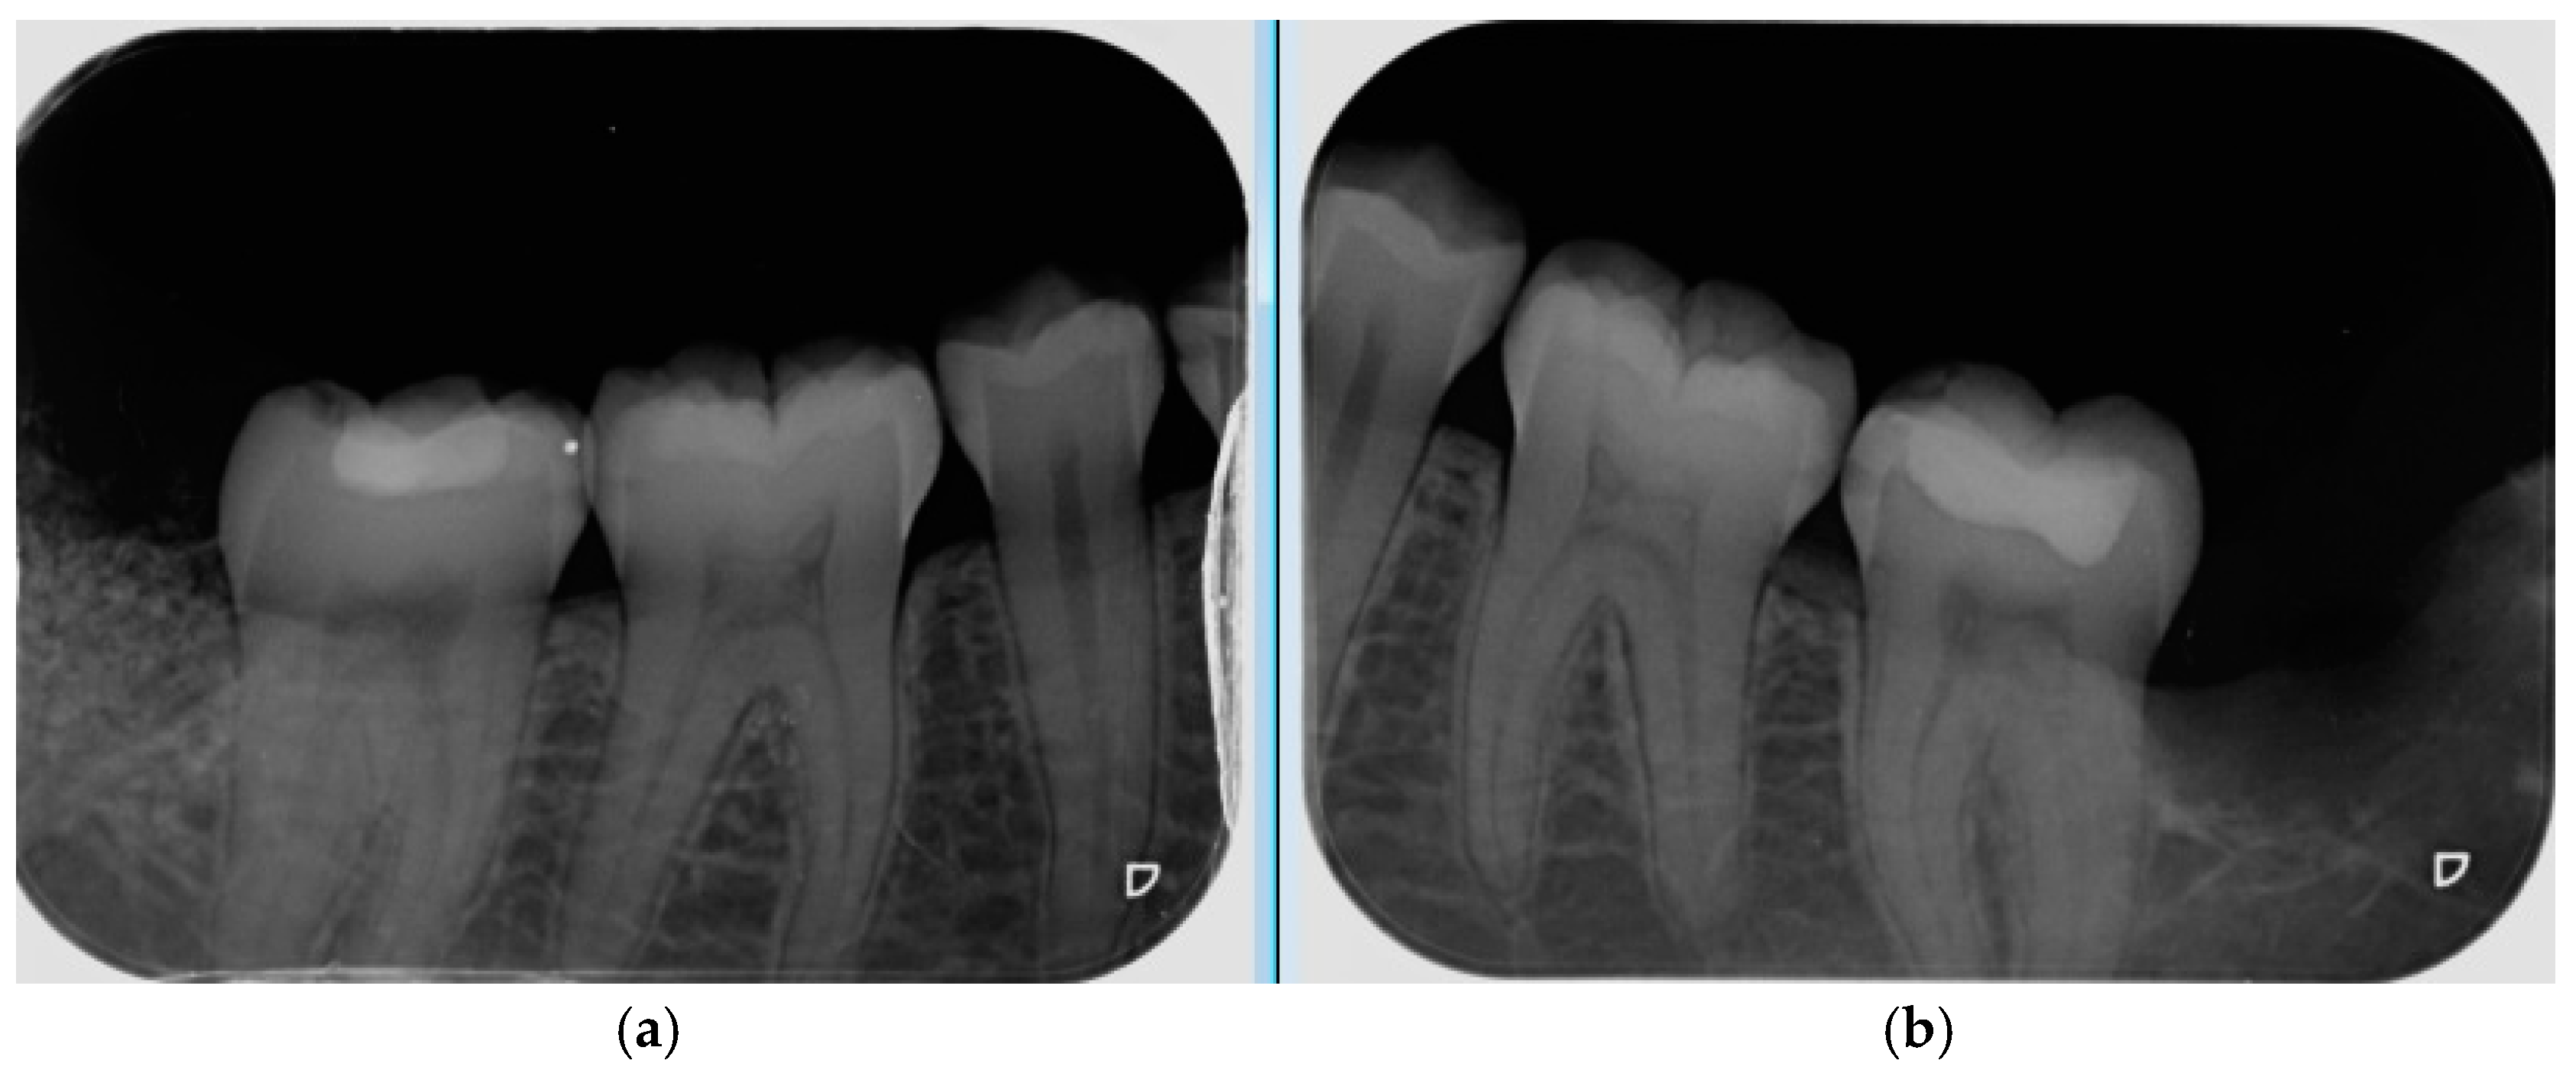

- Bone density, the degree of corticalization, and crestal bone height maintenance were measured 6 months after surgery on CBCT sagittal slices in all patients (Figure 6), using the same equipment (Newtom VGI evo, QR srl-Verone, Italy).

- Bone density was measured in Hounsfield units (HU) (Figure 7).

- The degree of corticalization was classified as complete (cortical ≥ 1 mm), incomplete, or absent (Figure 8).

- Distance from the IAN to the bone crest was measured at the distal aspect of the lower second molar, at the center of the third molar alveolus (Figure 9).